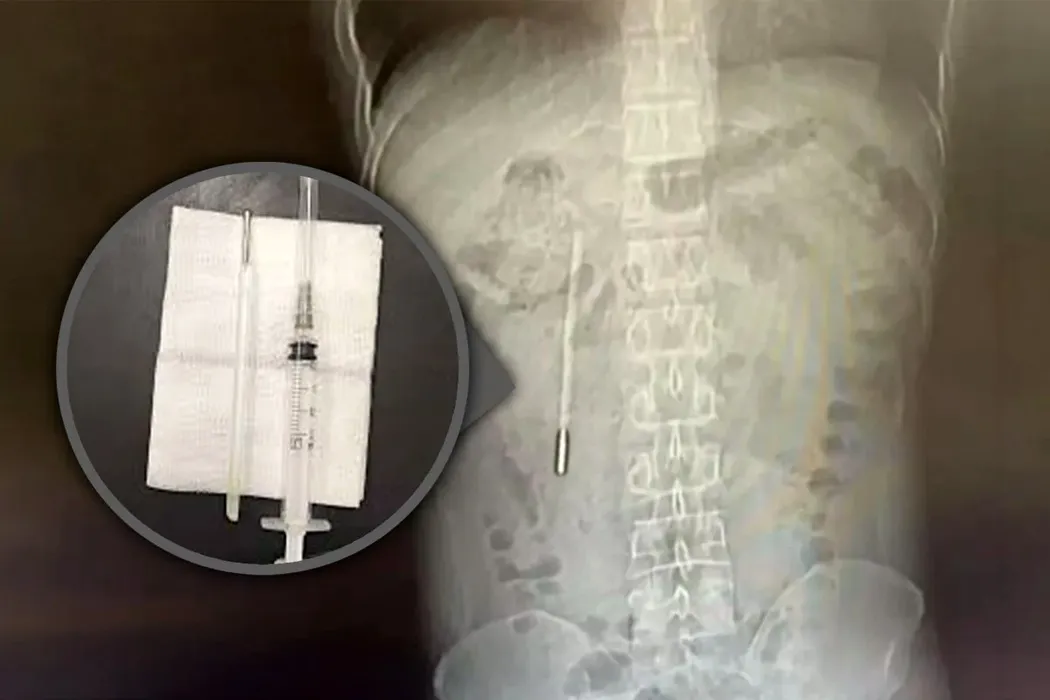

GALERIE FOTO: Un chinez a stat 20 de ani cu un termometru cu mercur în stomac. Anul trecut, doctorii au găsit o periuță de dinți